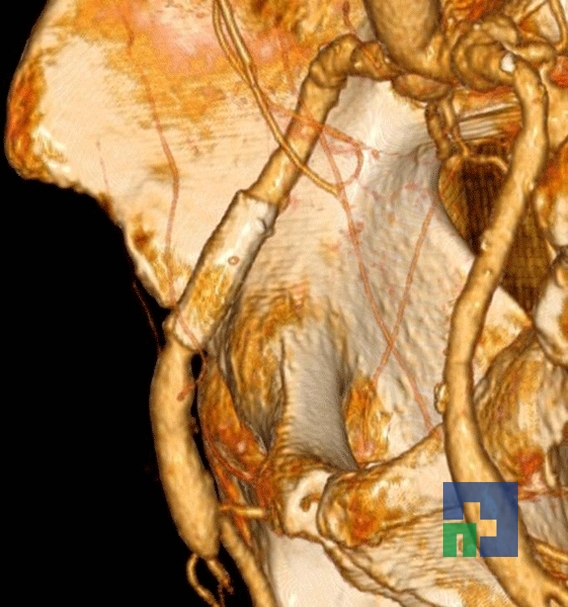

- Fistula carotido-cavernoasa